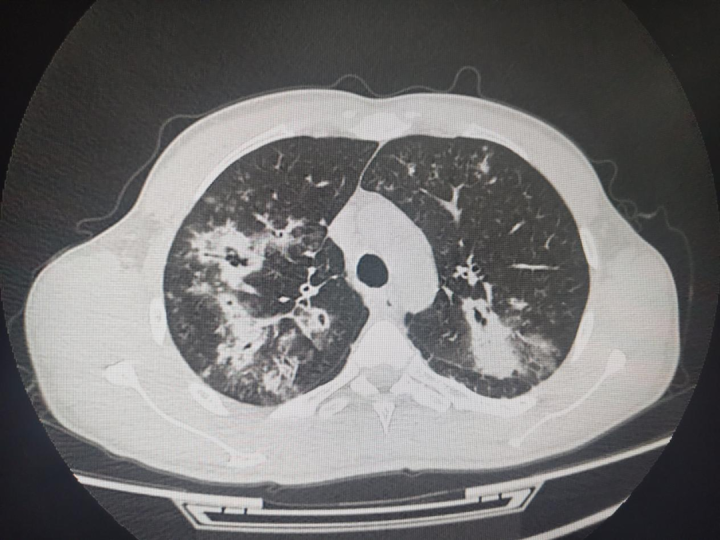

急性肺部感染,如吸入性肺炎、重症社区获得性肺炎等,作为急诊科的常见病与多发病,其治疗效果直接依赖于病原体的快速、准确诊断。然而,传统痰培养方法易受口腔菌群污染,导致病原体检出率低,可能引发误诊或治疗延误。相比之下,纤维支气管镜灌洗术通过直接获取下呼吸道分泌物——支气管肺泡灌洗液(BALF),不仅有效弥补了传统痰培养的局限性,更通过直接清除气道内的病原体及分泌物,显著提升了患者的康复速度与治疗效果。

据研究显示,采用肺泡灌洗液进行检测的患者,病原体阳性率高达80%以上,远超常规痰培养组的30%-50%,为急诊医生提供了更为可靠的诊断依据。在退热时间、咳嗽咳痰缓解时间、住院天数等关键指标上,纤维支气管镜灌洗术均展现出显著优势,优于常规治疗。